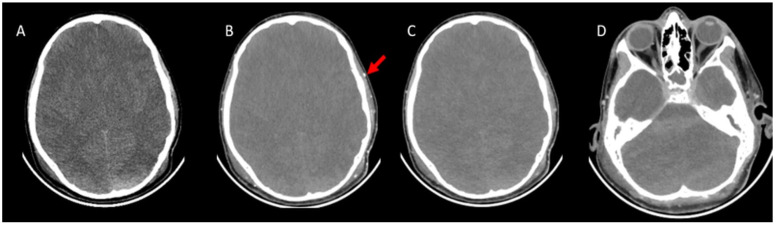

Background/objectives: While ancillary tests for brain death diagnosis are not routinely recommended in guidelines, they may be necessary in specific clinical scenarios. Computed tomography angiography (CTA) is particularly advantageous in pediatric patients due to its noninvasive nature, accessibility, and rapid provision of anatomical information. This study aims to assess the diagnostic sensitivity of a revised venous system (ICV-SPV) utilizing a 4-point scoring system in children clinically diagnosed with brain death.

Materials and methods: A total of 43 pediatric patients clinically diagnosed with brain death who underwent CTA were retrospectively analyzed. Imaging was performed using a standardized brain death protocol. Three distinct 4-point scoring systems (A20-V60, A60-V60, ICV-SPV) were utilized to assess vessel opacification in different imaging phases. To evaluate age-dependent sensitivity, patients were categorized into three age groups: 26 days-1 year, 2-6 years, and 6-18 years. The sensitivity of each 4-point scoring system in diagnosing brain death was calculated for all age groups.

Results: The revised venous scoring system (ICV-SPV) demonstrated the highest overall sensitivity in confirming brain death across all age groups, significantly outperforming the reference 4-point scoring systems. Furthermore, the ICV-SPV system exhibited the greatest sensitivity in patients with cranial defects.

Conclusions: The revised 4-point venous CTA scoring system, which relies on the absence of ICV and SPV opacification, is a reliable tool for confirming cerebral circulatory arrest in pediatric patients with clinical brain death.